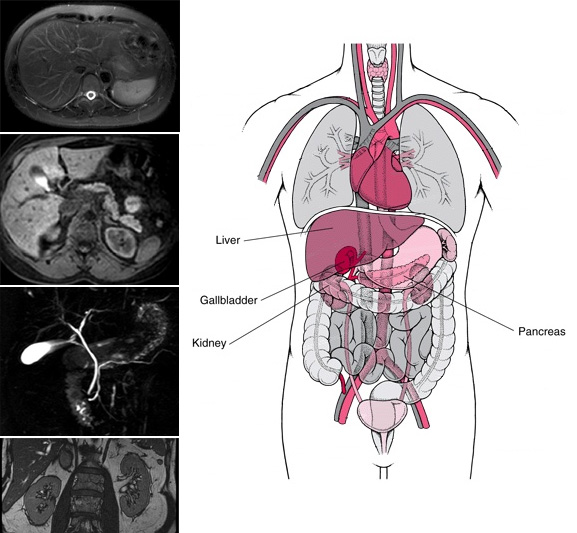

Магнитно-резонансная томография — один из наиболее совершенных способов диагностики. Мрт брюшной полости и забрюшинного пространства позволяет обнаружить опухоли, воспалительные процессы и скрытые кровотечения в том или ином органе, а также выявить изменения в его структуре. При помощи МРТ исследуются мягкие ткани стенок живота, печень, поджелудочная железа, селезенка, почки, желудок, мочевыводящие пути, желчный пузырь и лимфоузлы.

МР-обследование позволяет визуализировать печень, почки, все петли тонкого и толстого кишечника, поджелудочную железу, желудок, надпочечники, селезёнку, желчный пузырь, желчевыводящие пути, лимфоузлы, всю артерио-венозную системус оценкой движения по ней крови, лимфатические сосуды, нервы, метастазы, в т.ч. забрюшинного пространства. Особое место уделяется МР-холангиографии (получение объемного представления о состоянии внутри- и внепеченочных желчных путей без контрастирования) и безконтрастной МР-урографии.

Брюшная полость включает в себя огромное количество различных органов, и каждый из них подвержен своим заболеваниям. Помимо обследований на предмет отклонений в работе печени, почек, поджелудочной, селезенки, желчного пузыря и прочего, также МРТ этой области включает в себя исследование состояния расположенных здесь кровеносных сосудов.